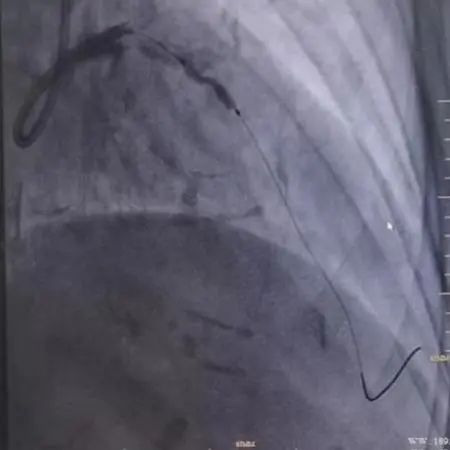

图2.病变处理前/普通球囊预处理中/冲击波球囊预处理中的冠脉造影图片对比

在6F EBU 3.5指引导管到位左冠后,沿前降支导丝送血管内超声(IVUS)导管无法通过病变,遂先予Sprinter 2.5×15mm球囊8atm扩张前降支病变,造影可见球囊膨胀呈“狗骨头现象”。球扩后再次送IVUS导管成功通过病变检查提示:病变处弥漫性纤维钙化斑块,局部可见180-330°钙化环,钙化厚度约0.2mm-0.4mm,长度约8mm,局部可见钙化小结。

该患者前降支病变迂曲、成角且钙化严重,单纯采用传统球囊扩张预处理可能存在病变扩张不完全,导致后续治疗风险加大;而采用冠脉内旋磨术有可能出现血管夹层闭塞或冠脉穿孔,手术风险高。经冠脉介入团队认真讨论,一致认为可采用冲击波球囊行IVL术处理该病变,以降低手术风险。

手术由黄进宇童国新两位教授联合实施。首先在前降支病变处置入3.5×12mm冲击波球囊,以4atm压力膨胀紧贴血管壁,然后启动脉冲发生器,持续激发10个脉冲完成第1周期,可见球囊逐渐膨胀充分,随后以6atm扩张冲击波球囊,可见球囊扩张满意。重新定位冲击波球囊,重复启动脉冲,总共7个周期脉冲优化冲击波碎石效果。